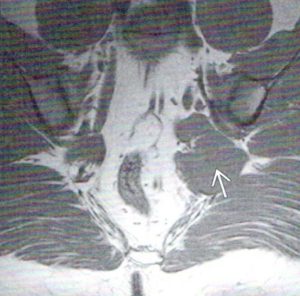

Figure 2 is a T-1 weighted axial image that demonstrates a grossly hypertrophic muscle belly (arrow). This was found in a patient who carried a large wallet in his left hip pocket and sat for long periods of time.